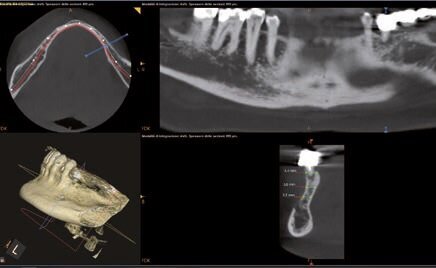

Fig. 3 - Misurazioni in sede 37.

Dopo aver valutato con la paziente tutti i pro e i contro abbiamo deciso di prediligere la scelta dei REX PiezoImplant. È stata eseguita un’impronta digitale che è stata accoppiata tramite il software di progettazione all’esame radiografico tridimensionale. Sono stati scelti due impianti REX PiezoImplant 1,8 x 11. L’impronta digitale della situazione pre-intervento della paziente ci ha permesso di utilizzare quest’ultima (come ceratura diagnostica) per programmare il posizionamento implantare in modo protesicamente guidato. La pianificazione software della fase chirurgica e l’utilizzo di una guida per il corretto posizionamento dell’impianto “asse implanto- protesico”, ci hanno permesso non solo di ottenere il posizionamento implantare nel rispetto dello spessore osseo disponibile “asse anatomico” ma anche di ricercare la migliore soluzione protesica avvitata, “asse protesico”, per una sensibile riduzione del rischio di errore. È stata creata una dima chirurgica che ci ha permesso di riportare nel cavo orale la programmazione dell’inserimento implantare che avevamo pianificato virtualmente. La metodica Rex permette di utilizzare una slitta che prevede una chirurgia guidata con sistema Pilot utilizzando l’inserto W2. Sono state raccordate le due preparazioni e le abbiamo estese con l’inserto OT7S3 che ci ha permesso di ottenere una maggiore elasticità ossea.